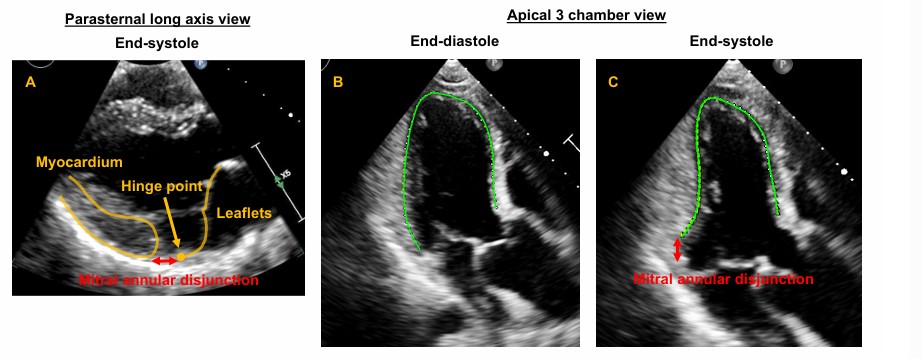

O prolapso foi definido como um deslocamento sistólico posterior (superior) do folheto valvar avaliado na janela paraesternal longitudinal eixo longo a partir do plano do anel mitral até o ponto mais superior do folheto prolapsado.

A disjunção do anel valvar (MAD) foi considerada como presente quando houve separação entre a borda posterior do miocárdio e a junção do folheto posterior com o átrio esquerdo (AE).

O curling consiste numa mobilidade exagerada do anel mitral posterior seguida de uma incursão miocárdica no segmento basal da parede ínfero lateral associado a um deslocamento superior do folheto posterior.